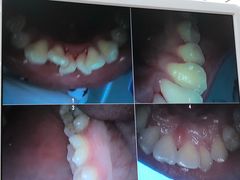

• 牙博士口腔(杨浦店)

• -牙博士口腔(杨浦店)